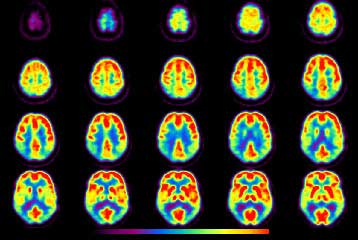

Τομογραφία για τη νόσο του Αλτσχάιμερ «εντοπίζει τα άτομα υψηλού ρίσκου»

Σικάγο: Τομογραφίες εκπομπής ποζιτρονίων (PET) δείχνουν ότι οι άνθρωποι με οικογενειακό ιστορικό της νόσου του Αλτσχάιμερ παρουσιάζουν συσσώρευση παθολογικών πρωτεϊνών στον εγκέφαλο ακόμα κι αν είναι απόλυτα υγιείς -αυτό σημαίνει ότι η εξέταση ίσως μπορεί να αναγνωρίζει τα άτομα υψηλού κινδύνου.